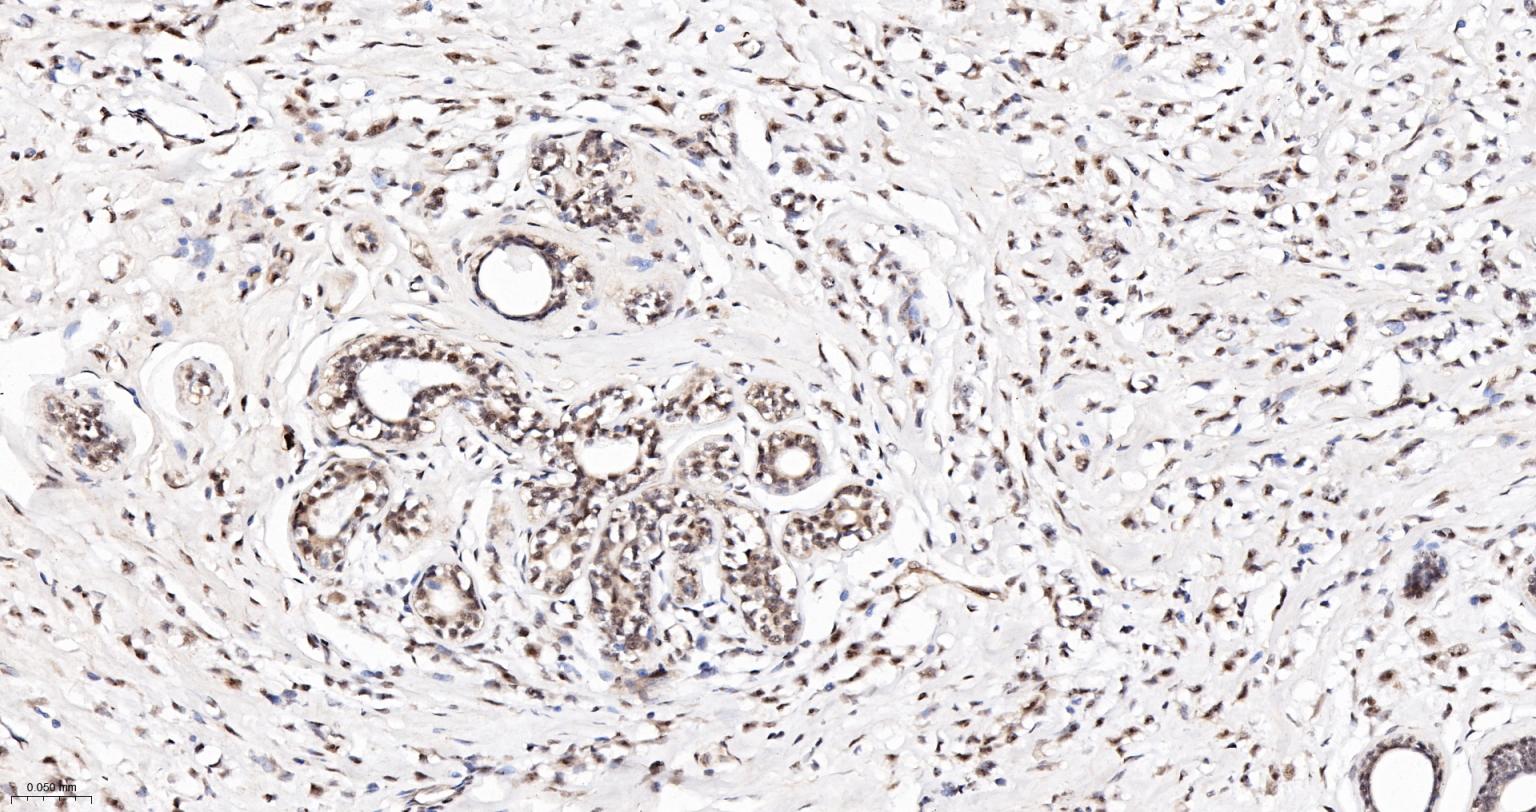

Paraformaldehyde-fixed, paraffin embedded Human Kidney; Antigen retrieval by boiling in sodium citrate buffer (pH6.0) for 15 min; The section was incubated with PELP1 Monoclonal Antibody, Unconjugated (bsm-61154R) at 1:200 overnight at 4°C, followed by conjugation to the bs-0295G-HRP and DAB (C-0010) staining.